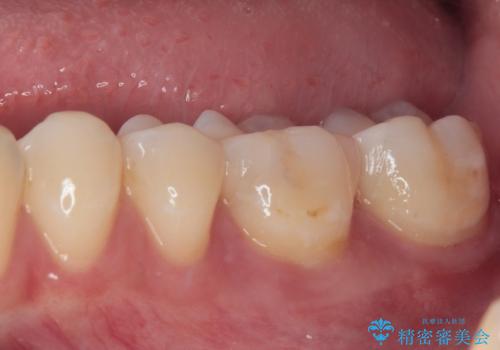

- 奥歯が食事の度にしみてしまうとのことで来院された患者様です。

目視やレントゲン写真からは、以前処置された部分に大きな問題は認められませんでしたが、冷たい風をかけると強い痛みを感じる状態でした。

患者様と相談の上、詰め物を全て外した上でむし歯があるかどうかを確認し、セラミックインレーで精密な修復治療を行うこととしました。